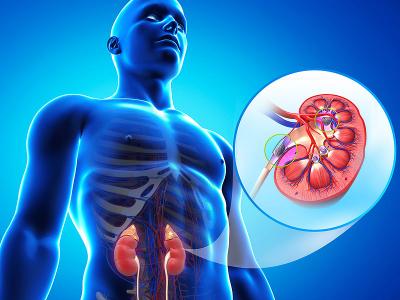

किडनी शरीर का मुख्य अंग है जिसका काम खून साफ करना, अनावश्यक जहरीले पदार्थों को पेशाब द्वारा बाहर निकालना, अपशिष्ट उत्पादों को निकलना, अम्ल एवं क्षार का संतुलन बनाना, खून के दबाव पर नियंत्रण रखना, हड्डियों को मजबूती प्रदान करना है। खराब खानपान के कारण किडनी से जुड़ीं कई बीमारियां तेजी से बढ़ रही हैं। इसमें से एक है किडनी की पथरी।

4) पेशाब रोककर रखना: कभी कभी काम करते हुए या किसी अन्य कारण से बहुत से लोग पेशाब को रोककर रखते हैं, ये किडनी के खतरनाक हो सकता है। इससे ब्लैडर भी असर पड़ता है जिससे आपको सिर्फ किडनी की पथरी ही नहीं बल्कि यूटीआई जैसी गंभीर समस्या भी हो सकती है।